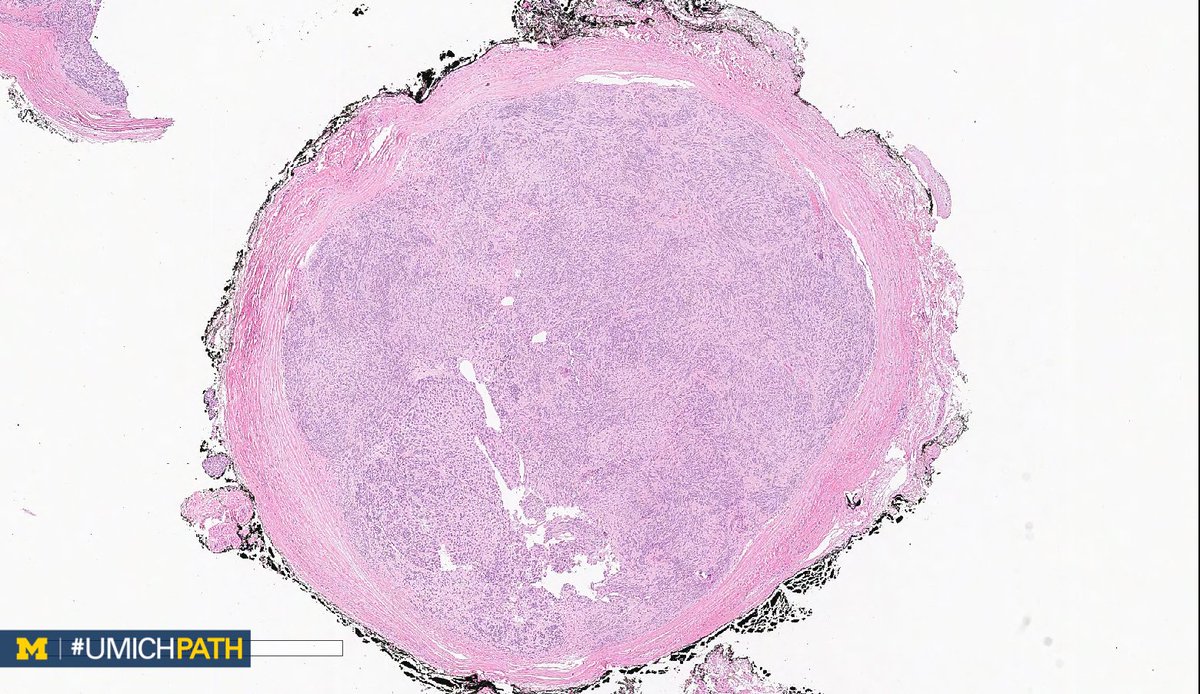

Bone and Soft Tissue #Pathology, day 2

What's your #DifferentialDiagnosis of this superficial soft tissue mass?

What #DailyDx do you favor, and what confirmatory stain(s) would you order?

We’ll tweet the answers and some quick facts tomorrow! #UMichPath#BSTPathpic.twitter.com/BkXUiAuRzg